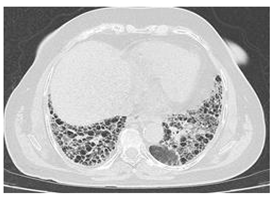

| Type of SARD-ILD | HRCT Features | Axial HRCT Images in Patients with SARD-ILD | Description of HRCT Images in Patients with SARD-ILD |

|---|---|---|---|

| SjS-ILD | NSIP; LIP with diffuse interstitial and peribronchiolar infiltration of lymphoplasma cells; OP. | ![]() | The appearance of LIP, commonly seen in patients with SjS, can be associated with ground glass lesions, nodules, septal thickenings, and cysts. The middle and lower lung fields are most frequently affected. |